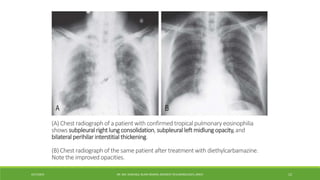

(A) Chest radiograph of a patient with confirmed tropical pulmonary eosinophilia

shows subpleural rightlung consolidation, subpleuralleft midlung opacity,and

bilateral perihilar interstitial thickening.

(B) Chest radiograph of the same patient after treatment with diethylcarbamazine.

Note the improved opacities.